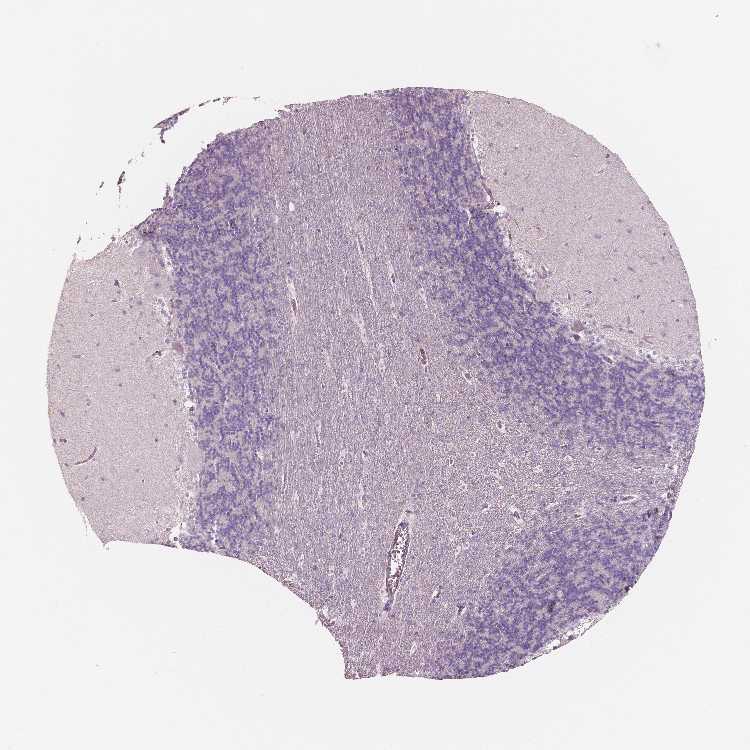

CEREBELLUM - Antibody stainingi

Antibody staining in the annotated cell types in the current human tissue is reported as not detected, low, medium, or high, based on conventional immunohistochemistry profiling in selected tissues. This score is based on the combination of the staining intensity and fraction of stained cells.

Each image is clickable and will lead to virtual microscopy that enables deeper exploration of all samples and also displays staining intensity scores, fraction scores and subcellular localization as well as patient and tissue information for each sample.

Antibody HPA001352Antibody HPA002549Antibody CAB068250Antibody CAB068251Antibody CAB068252

Purkinje cells Not detectedNot detectedNot detectedNot detectedNot detected

Cells in granular layer Not detectedNot detectedNot detectedNot detectedNot detected

Cells in molecular layer Not detectedNot detectedNot detectedNot detectedNot detected